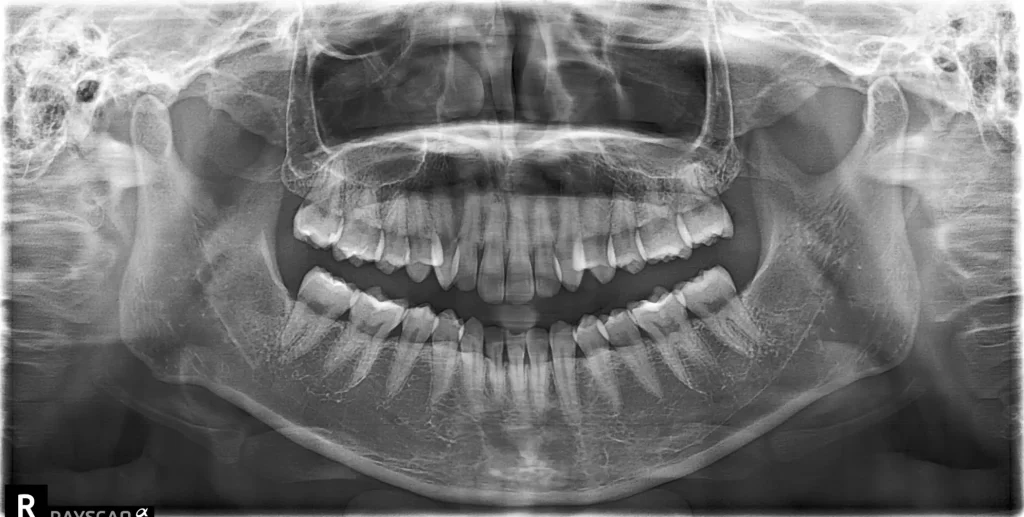

レントゲン撮影

当院では、年に1回パノラマエックス線写真を撮影しています。

この検査では、目で見ただけでは分からない部分を詳しく確認します。

たとえば、歯の根や顎の骨の状態をチェックします。

また、歯と歯の間に虫歯がないかも確認します。

このように、隠れたトラブルの早期発見につながります。

そのため、症状がなくても定期的な撮影がとても重要です。